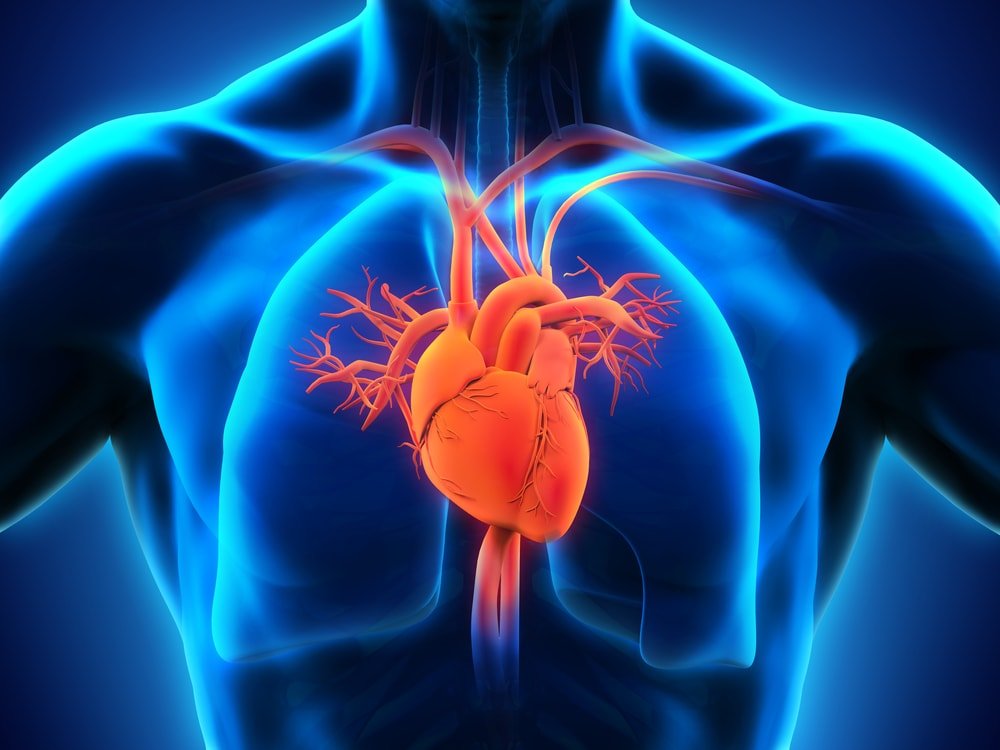

Prof. Philip Kolo of the Department of Medicine, University of Ilorin, on Friday postulated that Chronic Heart Failure (CHF) affects more than 64 million people worldwide.

He explained that heart diseases were progressive in nature (Cardiovascular continuum).

“It starts with the presence of a risk factor that is highly associated with Heart failure causing alterations in the size and shape of the heart,” according to him.